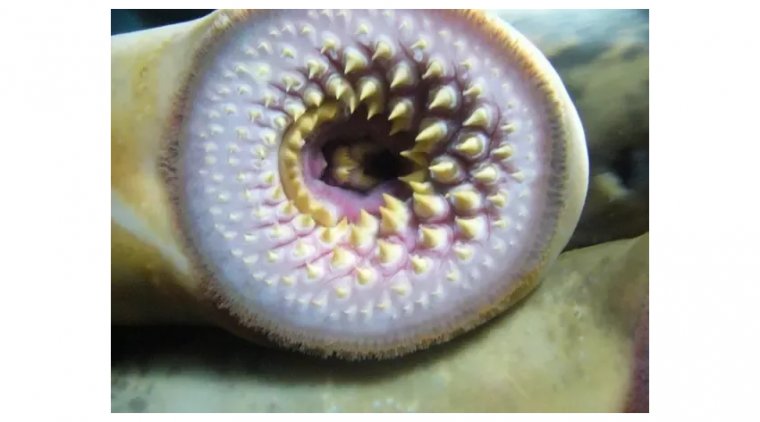

read moreLamprey Eye Disease, also known as "Lamprey Disease," is a hoax that has been circulating on the int...